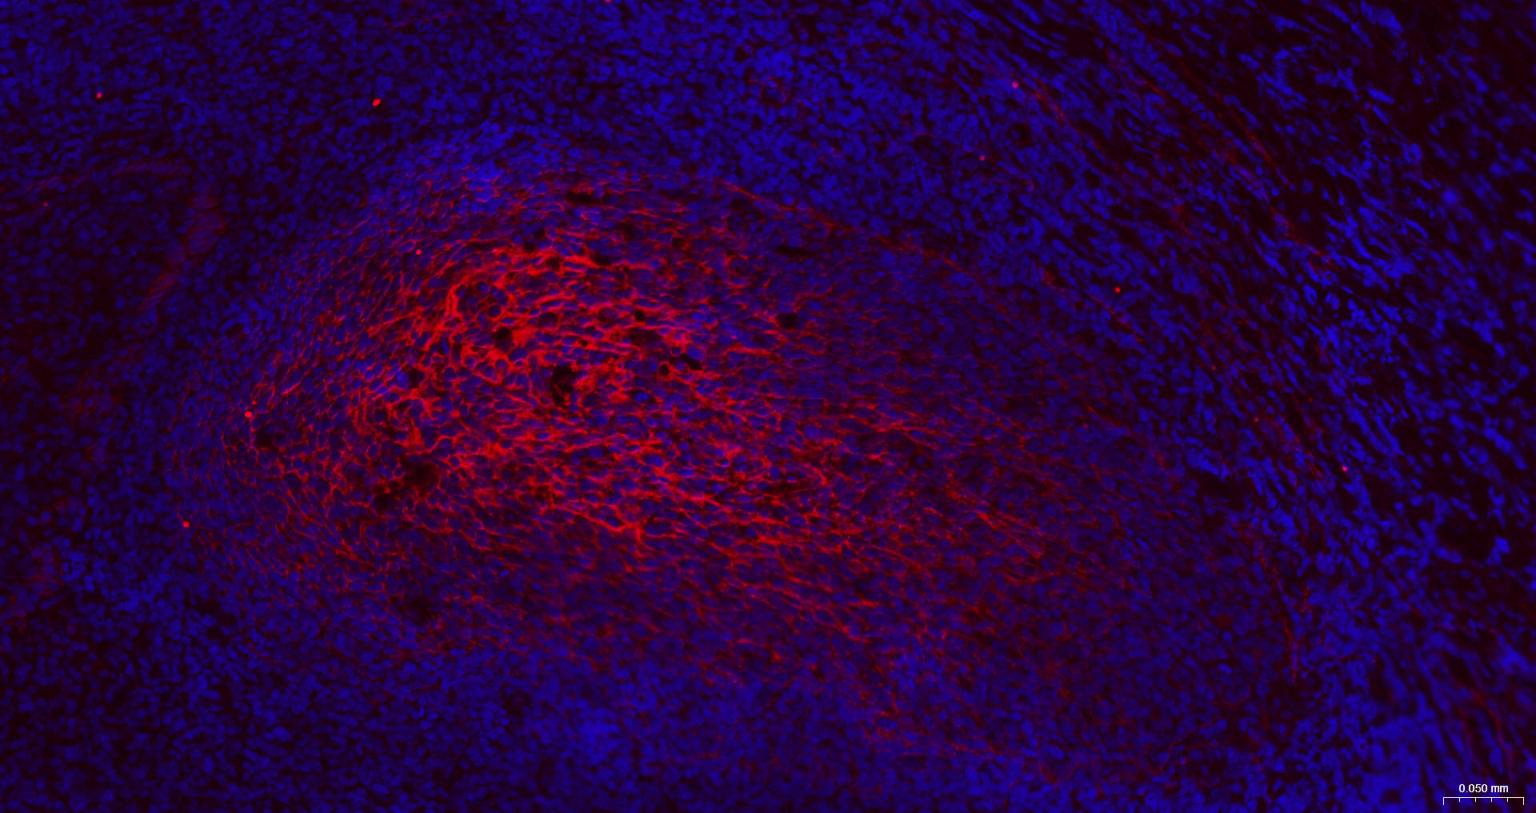

IHC-PHuman, Mouse, Rat1:100-500

IHC-FHuman, Mouse, Rat1:100-500

IFHuman, Mouse, Rat1:100-500

ICC/IFRatHuman, Mouse1:50-200